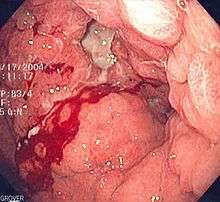

- Gastrointestinal

- Upper gastrointestinal bleed

- Lower gastrointestinal bleed

- Occult gastrointestinal bleed